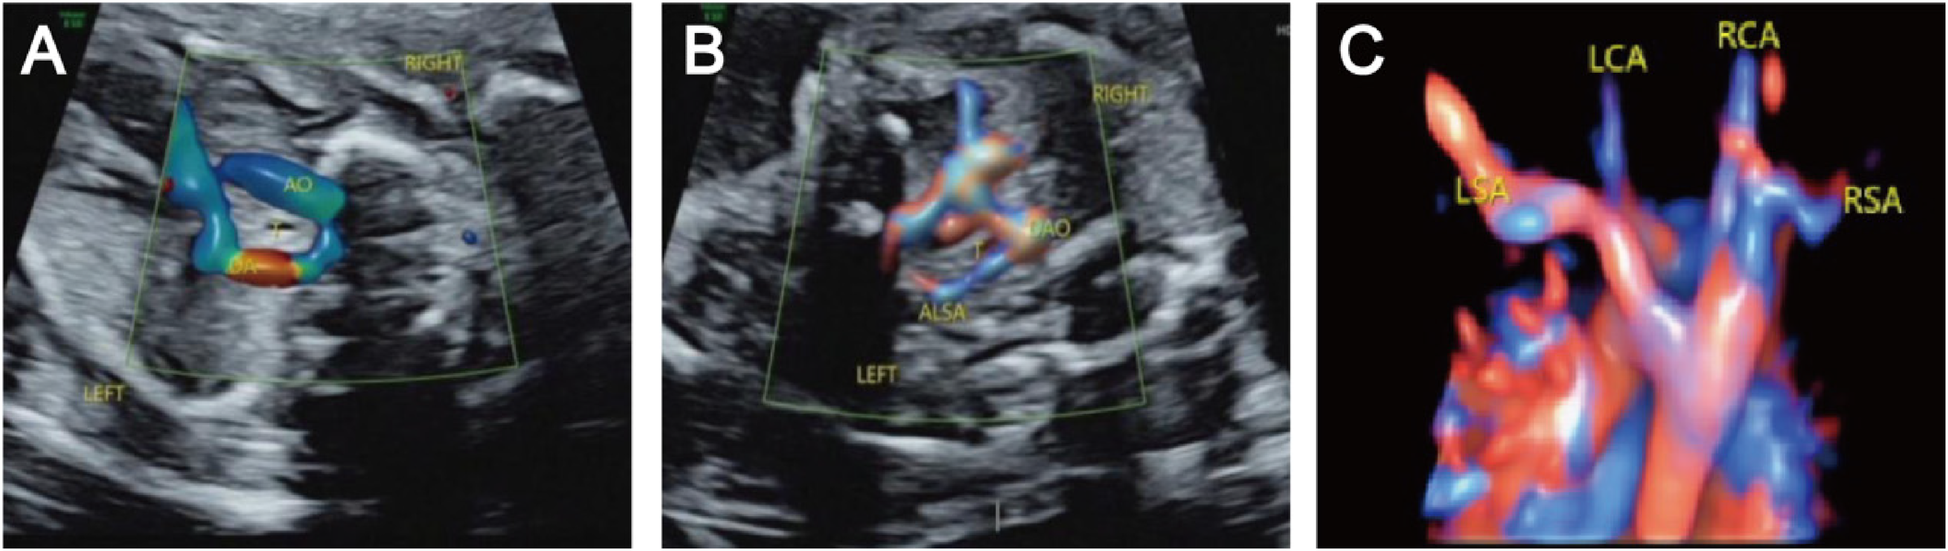

Figure 2

Right aortic arch with an aberrant left subclavian artery and left ductus arteriosus. (A) Three-vessel and trachea view showing that the aortic arch is located on the right side of the trachea, the ductus arteriosus and pulmonary artery are located on the left side of the trachea, and the “U” shaped blood vessels surround the trachea; (B) Bilateral subclavian artery view showing that the left subclavian artery starts from the beginning of the descending aorta, travelling obliquely towards the left arm at the back of the trachea, and forms a “C” shaped blood vessel with the aortic arch around the trachea; (C) STIC imaging showing that the four branches of the aortic arch are the left common carotid artery, right common carotid artery, right subclavian artery, aberrant left subclavian artery, and left subclavian artery starting from the beginning of the descending aorta and travelling left from the posterior trachea.